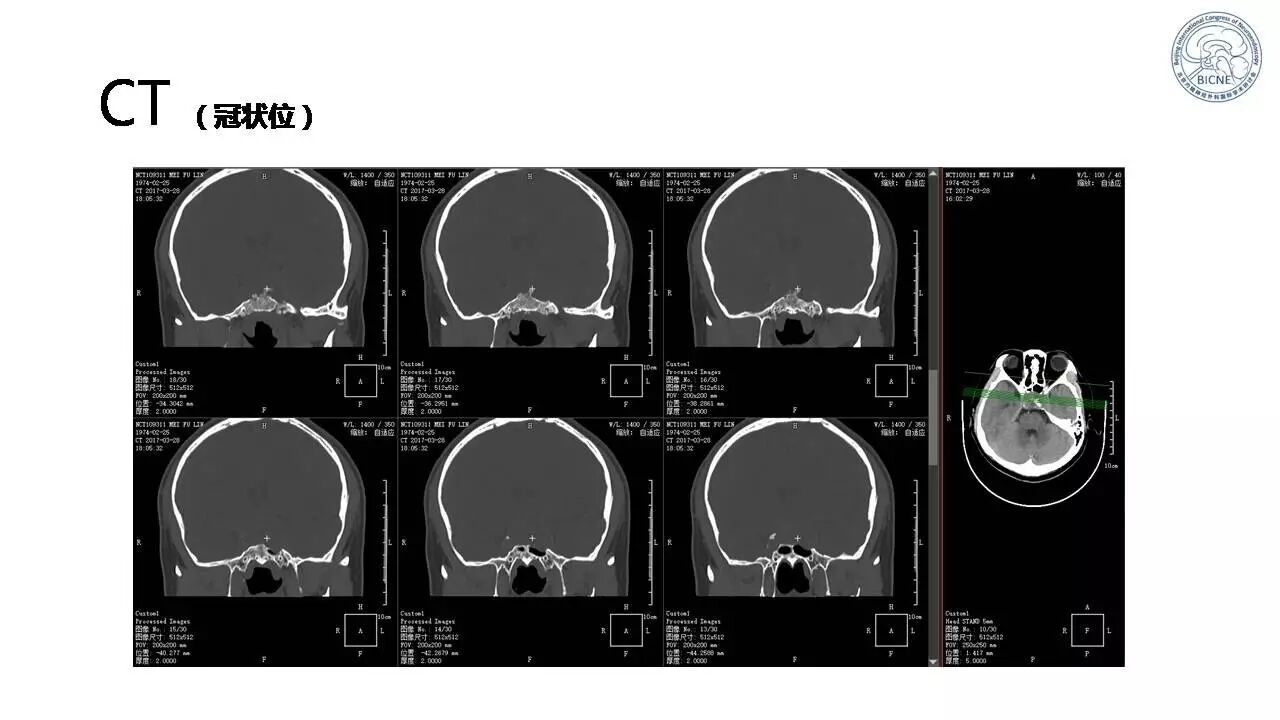

(一)张亚卓教授:脊索瘤经鼻内镜下治疗